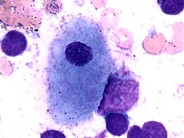

Pseudo-Gaucher cells Pseudo-Gaucher cells and sea-blue histiocytes can be seen due to increased cell turnover.